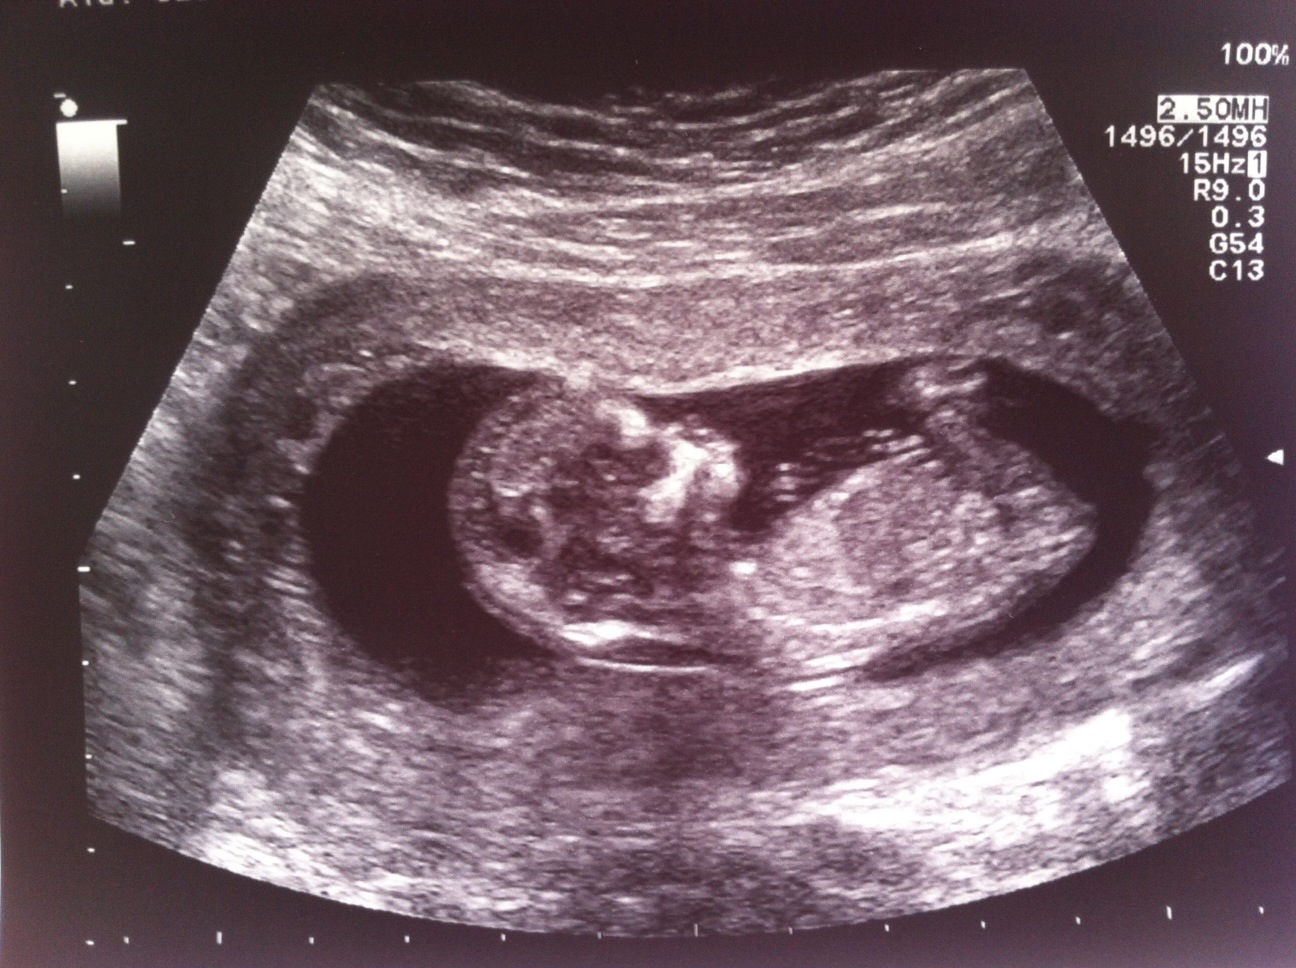

please can you see if there is a nub and can you guess gender? maybe based on skull if there is no nub? TIA

Skull looks girl!

I don't see a nub, but skull looks girly to me

based on skull- :babyf:

no nubby